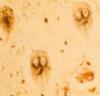

Histomonosis (histology)

Histomonosis (pathology)

Histomonosis (pathology)